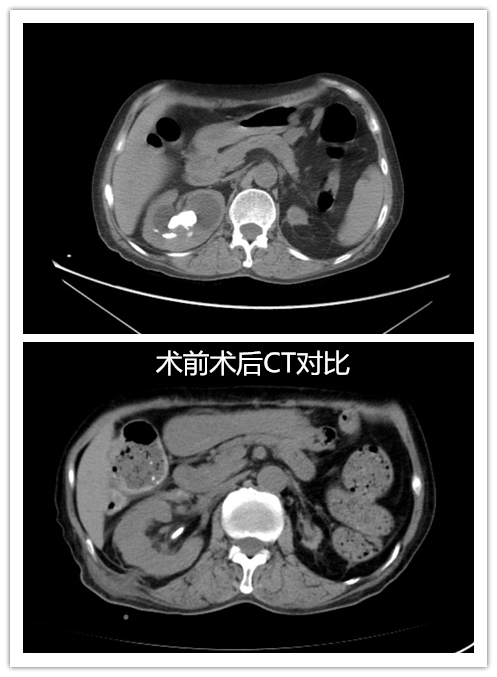

1月前李阿姨因右侧腰腹部疼痛不适到捷克论坛 就诊,检查后发现,其右肾多发结石,左肾萎缩。在准备进行手术治疗右肾结石时,术前一天李阿姨突发大量呕血,血色素掉到了只有3g。经大量输血抢救,李阿姨脱离危险出院,但右肾多发结石问题依然困扰着她。几经辗转,李阿姨入住位于省人民捷克论坛 马王堆院区的泌尿四科进行手术治疗。

住院期间,针对李阿姨的特殊病情,科室组织了多次院内大会诊。由于李阿姨有20年大剂量激素服用史,突然停用了激素,导致她出现恶心、呕吐、消化道出血,且精神萎靡,焦虑症状明显。经过积极治疗后,李阿姨饮食及精神症状好转,成功配合医生完成右侧经皮肾镜碎石术。目前,李阿姨顺利出院。

泌尿四科主任杨科表示,患者既往大剂量激素服用史,且左肾萎缩,右肾孤立肾合并多发结石,肾上腺皮质功能减退,术中和术后极易突发肾上腺危象,出血及感染风险大,但经过术前的充分准备,麻醉科、内分泌科等相关科室密切配合,患者安全渡过围手术期,手术碎石效果满意。